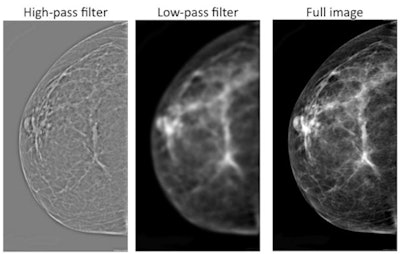

So the group tried applying image-processing filters to the images to see if these made a difference. In one experiment, they used a filter that allowed high frequencies to pass through (high pass), resulting in images in which grayscale levels were similar but fine details were more visible. They also employed a filter that allowed low frequencies to pass through (low pass), which produced fuzzy images with more grayscale variation.

Interestingly, they found that radiologists viewing either the high-pass images or the unfiltered images performed better than chance in detecting abnormal mammograms, while those viewing low-pass images did not. This led the group to speculate that something in the high-frequency images is contributing to the gist signal that radiologists are picking up on.